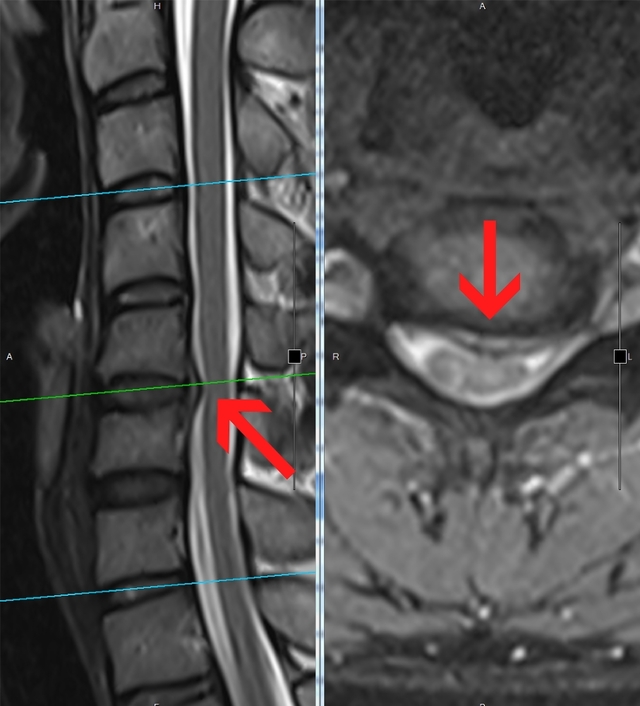

患者頸椎5至6節椎間盤突出。(翻攝光田綜合醫院官網)

林牧熹解釋,透過核磁共振檢查,發現張男頸椎5至6節椎間盤明顯突出壓迫神經,進而造成手不斷有痛、麻等感受,經評估,進行手術,以及1周休養時間,張男這才終於順利返回職場。